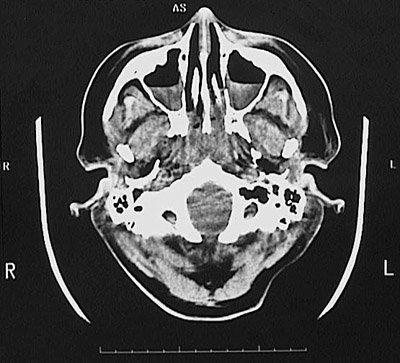

This is a normal head CT scan demonstrating the base of skull with the maxillary sinus and zygomatic bone and nasal cavity and septal cartilage and mandible and external auditory canal and mastoid air cells and cerebellar tonsils.